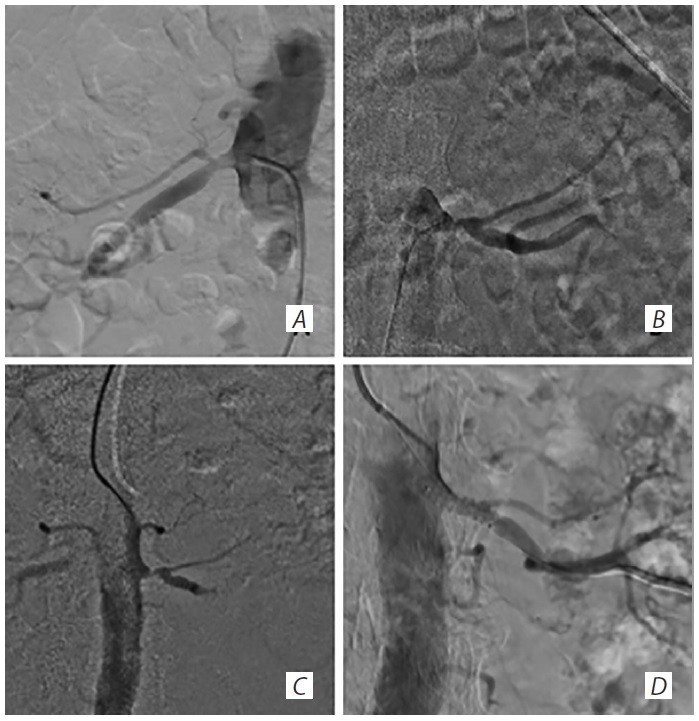

Под местной анестезией в общей СА позиционирована система проксимальной защиты МоМа 9Fr. В М1 сегмент средней мозговой артерии проведён проводник 0,014 дюйма (рис. 5, А). После раздутия баллонов системы проксимальной защиты выполнена баллонная ангиопластика стеноза кавернозного сегмента ВСА баллонным катетером 3,0 × 20 мм (рис. 5, B). Далее в зоне остаточного стеноза имплантирован коронарный голометаллический стент 4,0 × 26 (рис. 5, D, E). В зоне нестабильной бляшки в сегменте С1 позиционирован конусный каротидный стент 6,0–8,0 × 40 мм (рис. 5, F). Выполнена имплантация с последующим удалением доставочной системы стента с вакуум-аспирацией (40 мл). В аспирате фрагментов бляшки не обнаружено.

Рис. 5. Реваскуляризация СА пациента М. А — проводник расположен в средней мозговой артерии; В — ангиопластика ВСА в С4 сегменте; С — ВСА после баллонной ангиопластики С4 сегмента; D — позиционирование стента в зоне остаточного стеноза ВСА; Е — ВСА после стентирования С4 сегмента; F — стентирование ВСА в С1 сегменте. / Fig. 5. Transcarotid artery revascularization in patient M. А — guidewire positioning in MCA; В — ICA C4 angioplasty; С — ICA post C4 angioplasty; D — stent positioning in the area of ICA residual stenosis; Е — ICA post C4 stenting; F — С1 ICA stenting.

Контрольная ангиография показала удовлетворительное позиционирование стентов, кровоток по бассейну правой ВСА — TICI3 (рис. 6).

Рис. 6. Ангиография пациента М. до (А) и после (В) реваскуляри- зации. Усиление кровотока по средней мозговой артерии (чёрный контур на фрагменте В) после стентирования. / Fig. 6. Patient M.'s angiography before (А) and after (В) revasculari- zation. Increased MCA blood flow (В black outline) post stenting.